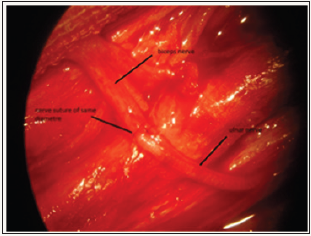

There were 19 men and 02 women; the mean age was 36 years (range 08-65 years). The most common mechanism of injury motor vehicle collision (17 patients), followed by motorcycle accident (03 patients) and a road accident (1 patient). Surgery was performed at mean of 15 months after injury (range 03-25 months). All patients benefited from a double nerve transfer (transfer of motor fascicles of the ulnar nerve to the nerve of the biceps with same diameter, combined with a transfer of motor fascicles of the median nerve to the nerve of the brachial with same diameter) “Figure 1 & 2” according to the technique of Oberlin [2], with the objective of restoring elbow flexion.

Figure 1: up the nerve of the biceps, below motor fascicleof the ulnar nerve with same diameter, between the nerve suture.